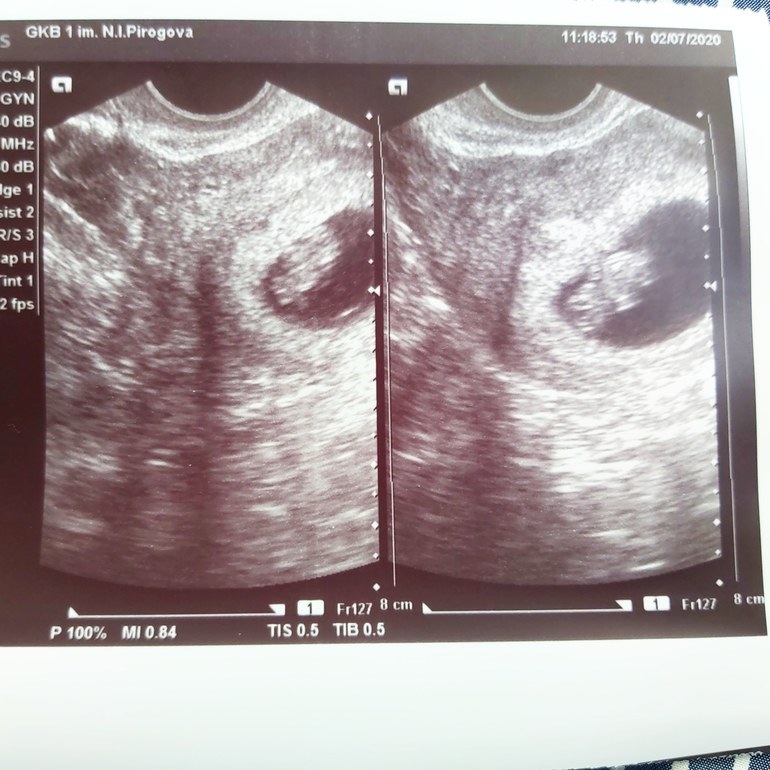

Через живот:

Это через живот, вроде зеркально надо смотреть относительно вагинального узи. Ну, посмотрим ))